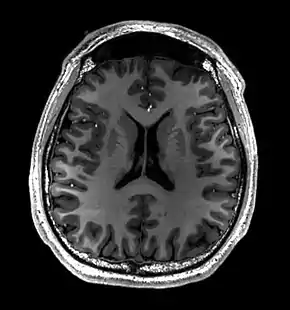

Brain regions on T1 MRI

Normal axial T2-weighted MR image of the brain